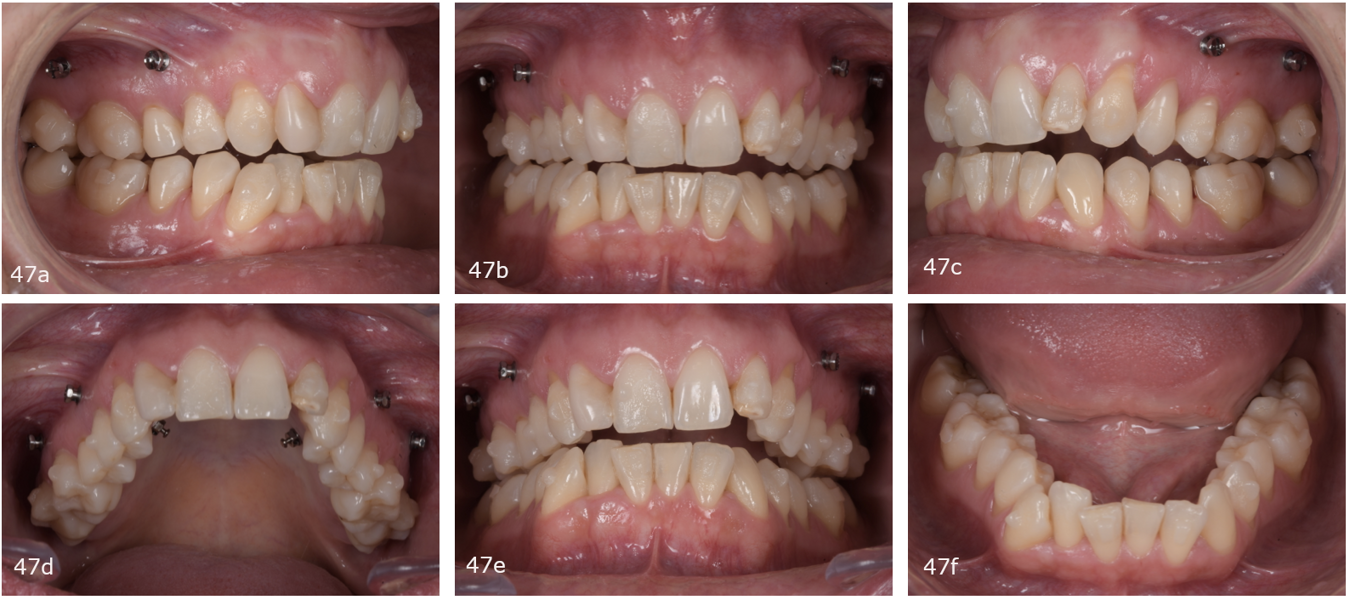

The first phase consisted of 26 maxillary and mandibular aligners. After the attachments had been cemented, six micro-screws were placed (four buccal screws between the maxillary first and second molars and between the maxillary first and second premolars and two palatal screws between the maxillary second premolar and first molar), and the patient was instructed to use 5⁄16 in. and 8 oz elastics to help in the intrusion of the posterior teeth (Fig. 47). At the 16th pair of aligners, we introduced the STOP and GO concept. After STOP and GO at the 17th pair of aligners, we decided to continue, since the treatment was progressing correctly.

Because the treatment had distributed the spaces between the maxillary incisors, it was decided to provisionally restore the lateral incisors (Fig. 48). After the incisors had been restored with provisional composite, we scanned the patient for new aligners to initiate the second phase. In this phase, we expanded the maxillary and mandibular arches, continued the postero-superior intrusion to close the open bite by mandibular auto-rotation and finalised the alignment (Fig. 49). This stage consisted of 20 pairs of aligners (Fig. 50). We finished the case with a third phase of ten pairs of aligners and incorporated inter-maxillary elastics (Fig. 51).

After treatment, the patient had bilateral Class I molar and canine relationships, correct overjet and overbite, centred midlines and improved arch forms (Fig. 52). Extra-orally, she had improved arch forms, a wider smile, an improved smile line and less gingival exposure (Fig. 53). The lower facial third had been shortened thanks to mandibular antero-rotation, and there was improvement of the upper lip support thanks to the positive torque of the maxillary incisors. In the post-treatment panoramic radiograph, we observed excellent periodontal status, no resorption of the roots and extraction of the maxillary third molars (Fig. 54). In the post-treatment cephalometric tracing, we saw a decrease of the ANB angle, a reduction in the anterior face height, an increase of the facial axis angle, and a decrease in the distance between the soft pogonion and the true vertical line thanks to the anticlockwise rotation of the mandible (Fig. 54). We also found an increase in the inclination of the maxillary incisors and an improvement in the final inter-incisal angle. Concerning her TMJs, the patient remained totally asymptomatic and had a vertical masticatory pattern and a stable arc of closure. The CBCT scan showed well-corticated condyles in the same position as that obtained after the splint therapy (Fig. 56).